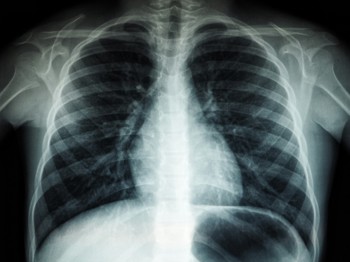

£1.2m was awarded to Cheshire and Merseyside from the AIDF to accelerate the implementation of an AI imaging and support tool which can analyse chest X-ray images and identify possible signs of lung cancer.

The technology is supplied by Annalise.ai a global health company offering AI solutions for clinicians. Annalise.ai’s technology uses AI to facilitate fast, accurate detection of up to 124 clinical findings and act as a second pair of eyes for clinicians helping them to ensure an accurate diagnosis of lung cancer patients more quickly.

Initial feedback from CAMRIN users has been very positive with clinicians recognising the value of detection capabilities and the many benefits that the new technology will provide to patients. When the AI technology identifies a potential lung cancer case, the information is relayed to the radiologist in under a minute. If they confirm the solution’s findings, the patient is booked for a CT scan on the same day, fast tracking both diagnosis and treatment.